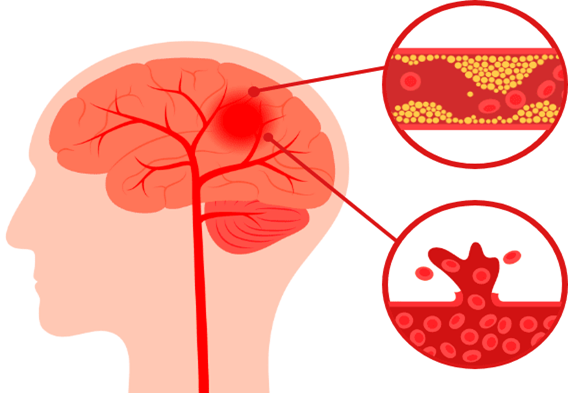

뇌졸중 (중풍)

뇌혈관 이상으로 갑자기 발생하며, 손발의 마비 증상 및 호흡 곤란 등의 증상이 나타나는 질환입니다.